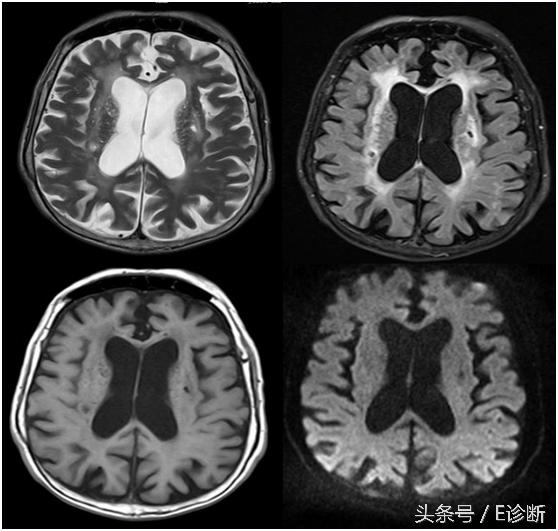

右侧基底节区多发腔隙性脑梗塞形成软化灶,周围见胶质细胞增生。

皮层下动脉硬化性脑病,脑萎缩脑沟增宽加深脑室增大,双侧放射冠多发腔隙性脑梗塞部分已软化,双侧脑室周围对称性条带状异常信号。